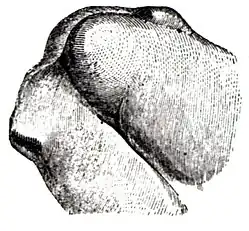

Manchmal macht die röntgenologische Abgrenzung der Patellafraktur von einer Patella partita (lat.: zweigeteilte Kniescheibe), also einer während der Entwicklung ausgebliebenen Verschmelzung der Knochenkerne, diagnostische Schwierigkeiten. Während sich frische Frakturen scharfkantig abbilden, findet man bei der Patella partita abgerundete Kanten, die „Fragmente“ sind nicht miteinander kongruent. Auch fehlt bei der Patella partita in der Regel der typische klinische Befund einer Patellafraktur, es besteht keinerlei Funktionsverlust. Wichtig ist die Unterscheidung für die Indikation zur Operation: Nur die frische Fraktur profitiert von der OP.

Differentialdiagnose Patella bipartita: Im Gegensatz zur Längsfraktur (s. unten) abgerundete Kanten der Fragmente

Differentialdiagnose Patella bipartita: Im Gegensatz zur Längsfraktur (s. unten) abgerundete Kanten der Fragmente -